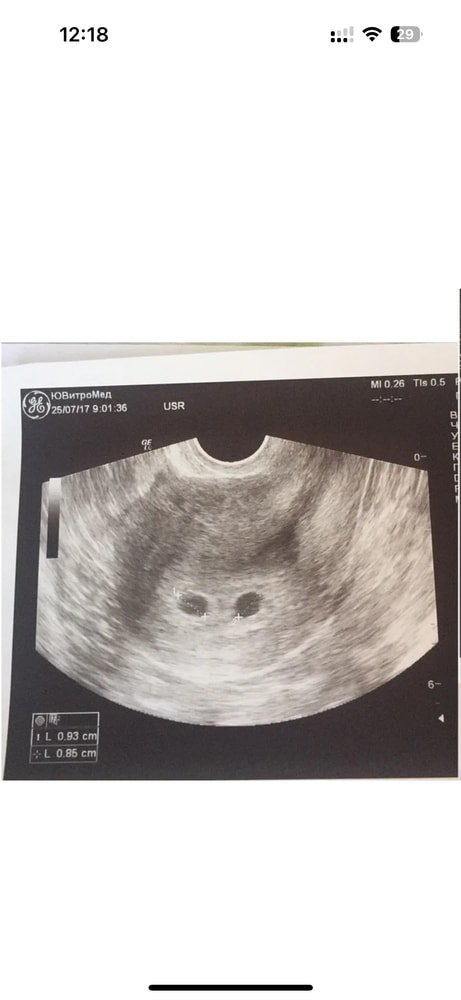

ДиДи двойня срок 4-5 недель

КС и ЕР при двойне.Узи прилагаю.

Девочки всем привет. Вчера узнала что два плодных яйца. Желтое тело одно. В одном эмбрион есть и сб есть

в др ничего не видно еще!